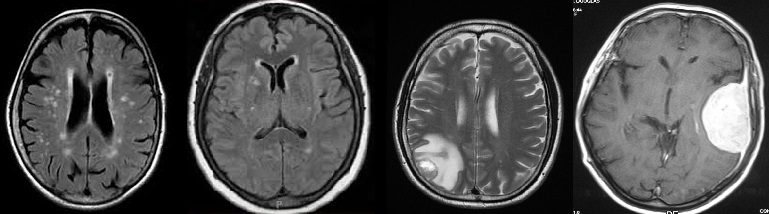

In our second set of experiments we use brain tumor dataset from Kaggle222https://www.kaggle.com/datasets/navoneel/brain-mri-images-for-brain-tumor-detection. The dataset consists of 253 brain MRI images, categorized into two groups: images with brain tumors and those without. Each image is provided in JPEG format with varying resolutions. Figure 7 presents a selection of sample images from the dataset.

Refer to caption

Figure 7: Sample images from the Brain MRI dataset.